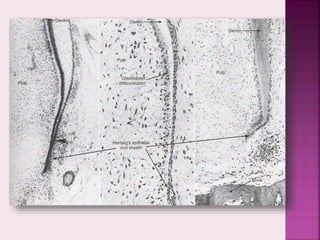

3 Fate of epithelial root sheath

• After dentine formation in root takes place, the epithelial

root sheath breaks down and its remnants migrate away

from the dentinal surface

• They lie in the periodontal ligament and are called epithelial

rests of Malassez

• The epithelial rests of Malassez are found the in the

periodontal ligament through out the life